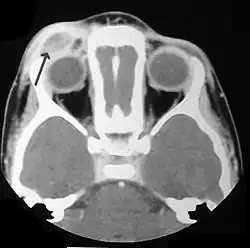

Imaging may be evident in chest X-rays with micronodular and reticular changes of the lungs with cyst formation in advanced cases. MRI and High-resolution CT may show small, cavitated nodules with thin-walled cysts. MRI scan of the brain can show three groups of lesions such as tumourous/granulomatous lesions, nontumourous/granulomatous lesions, and atrophy. Tumourous lesions are usually found in the hypothalamic-pituitary axis with space-occupying lesions with or without calcifications. In non-tumourous lesions, there is a symmetrical hyperintense T2 signal with hypointense or hyperintense T1 signal extending from grey matter into the white matter. In the basal ganglia, MRI shows a hyperintense T1 signal in the globus pallidus.[37]